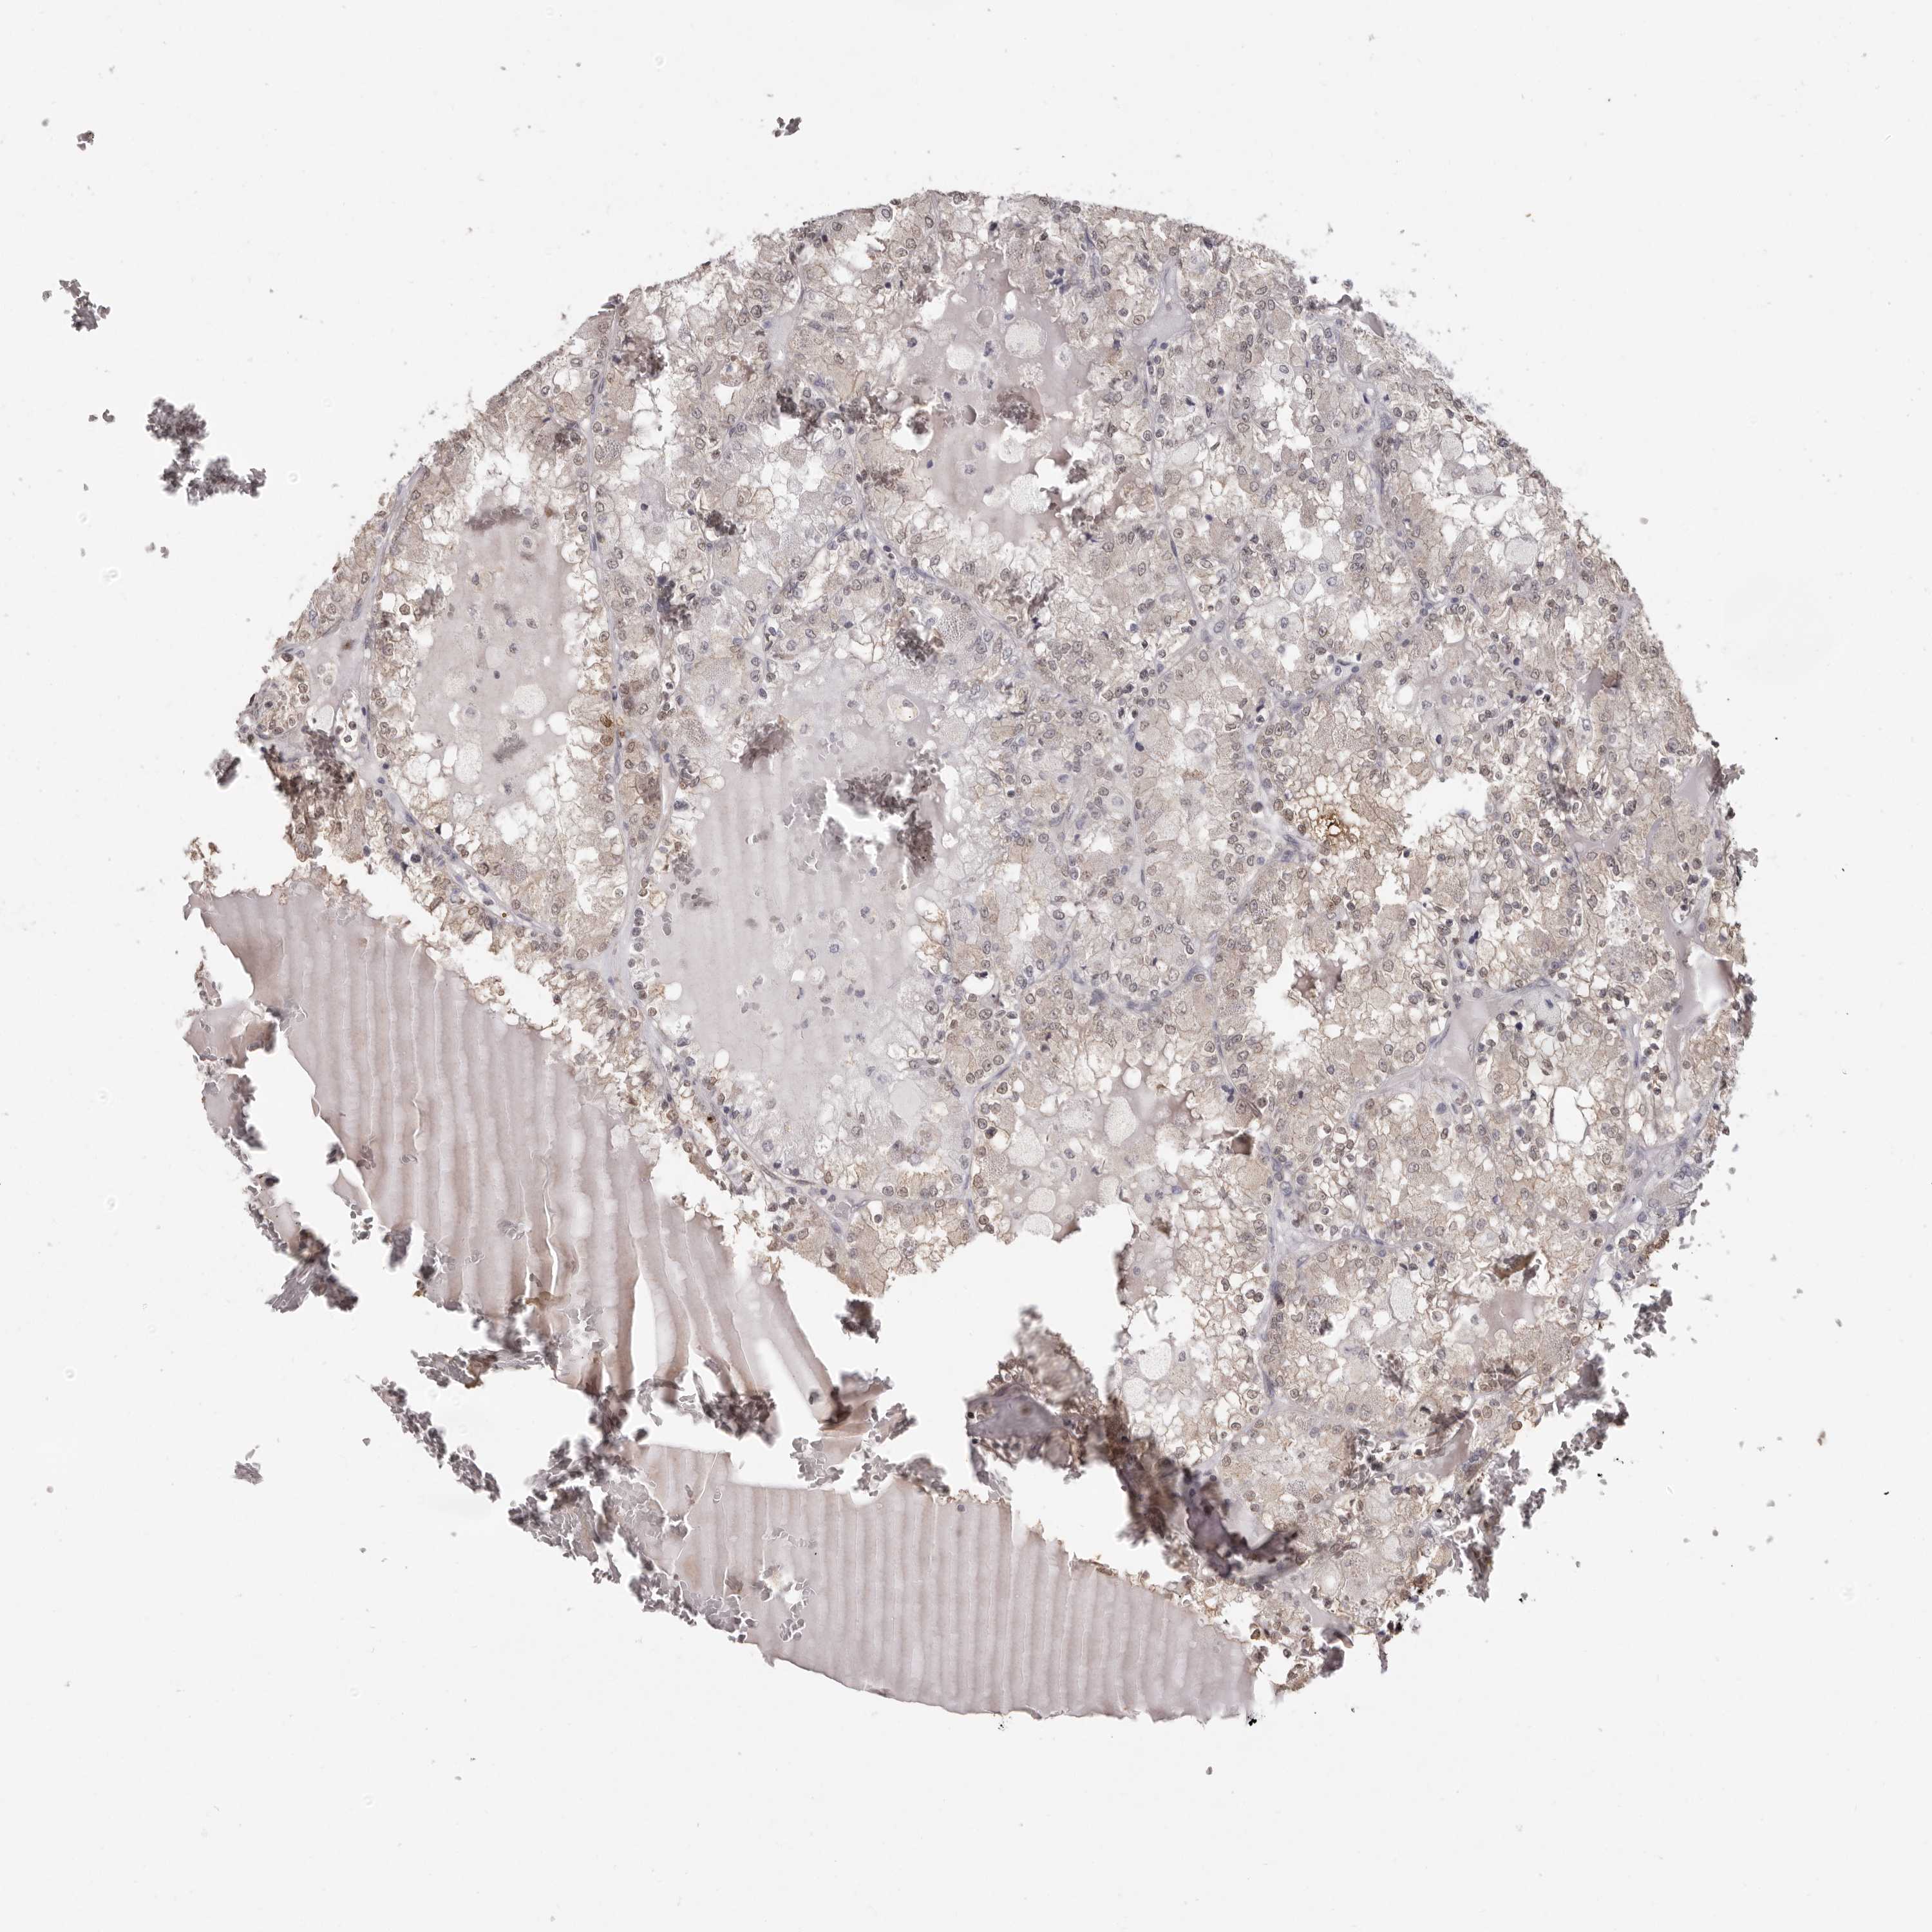

CANCER RENAL CANCER Show tissue menu

KICH TCGA KIRC TCGA KIRC VALIDATION KIRP TCGA PROTEIN RCC CPTAC PROTEIN EXPRESSION